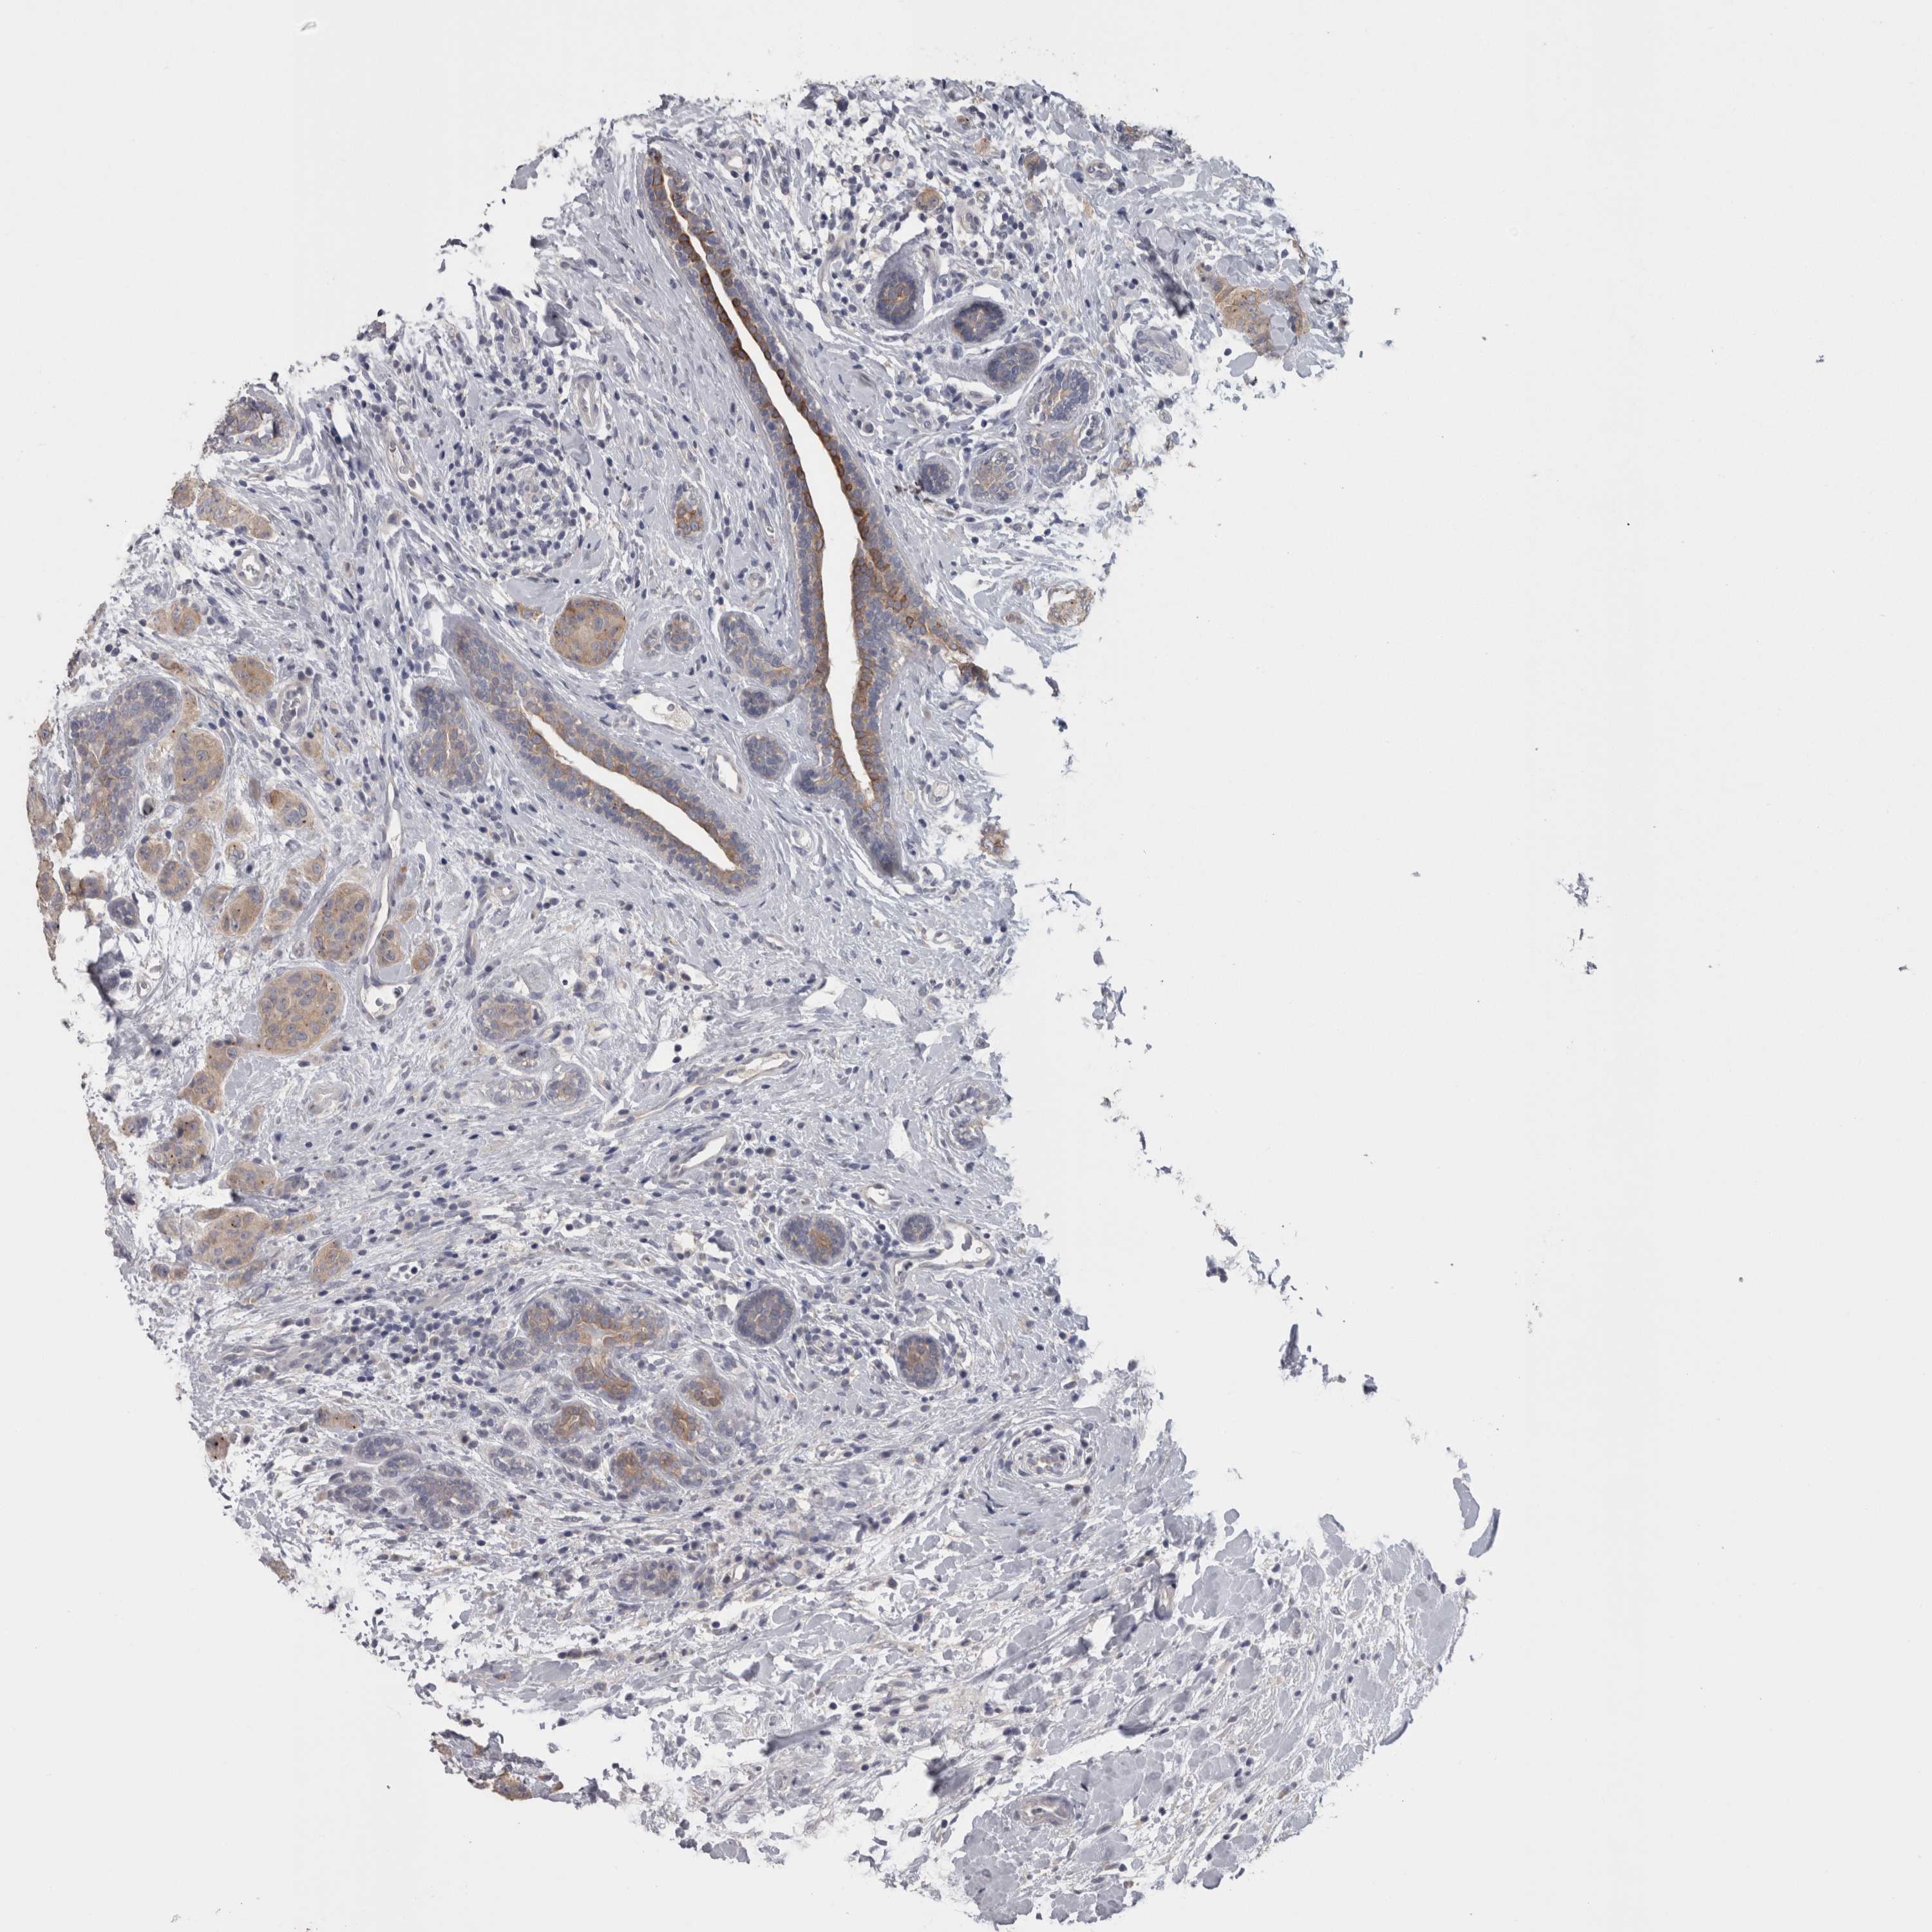

CANCER BREAST CANCER Show tissue menu

BRCA TCGA BRCA VALIDATION PROTEIN EXPRESSION